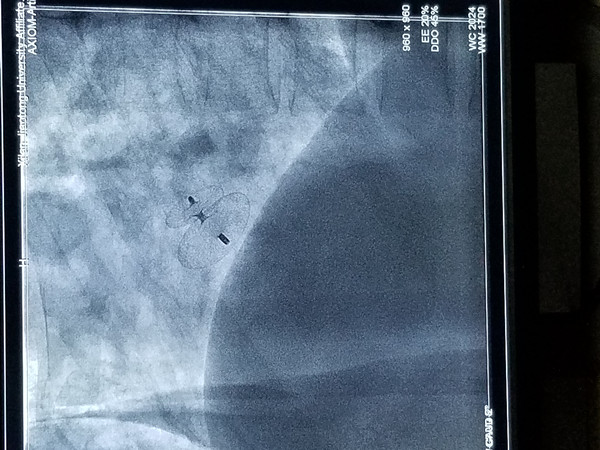

卵圆孔一般在生后第1年闭合,若大于3岁的幼儿卵圆孔仍不闭合称卵圆孔未闭,成年人中约有20%~25%的卵圆孔不完全闭合。诊断主要靠心脏超声检查来明确诊,其多种治疗方法中,药物治疗仅在缺血事件发生后起挽救或预防缺血复发的作用,手术缝合因创伤大临床上未曾推广,而经皮介入PFO封堵术却具有安全、有效、创伤小的优点。从大腿根部腹股沟区穿刺股静脉,循人体自身大血管路径(股静脉→髂外静脉→髂总静脉→下腔静脉→右心房)将封堵器送达并固定于未闭的卵圆孔处,PFO封堵术主体部分耗时约5-10分钟,术后仅在大腿根部留有针眼大小穿刺伤口,术后半年PFO平均闭合率可超过98%。

经充分术前准备,3月20日晚8时许,张宇顺主任医师与我院董新主任医师为宋先生进行了PFO封堵术,手术过程顺利。术后复查心脏彩超提示“心房水平静息与负荷状态下均未见右向左分流”。患者术后恢复良好,心悸、气促及头痛症状明显改善。